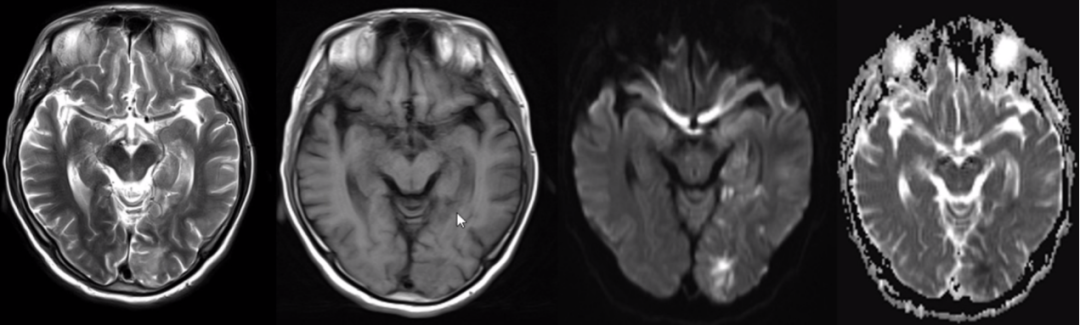

(3)静脉性脑梗死

MRI 表现与硬膜窦内血栓、静脉回流受阻造成的继发性脑实质改变有关:

脑实质改变包括水肿、出血灶。

脑白质(灰白质交界)出血。

DWI 表现不尽相同。

不同血管分布。

如下图可见案例:静脉性脑梗死与动脉性脑梗死对比